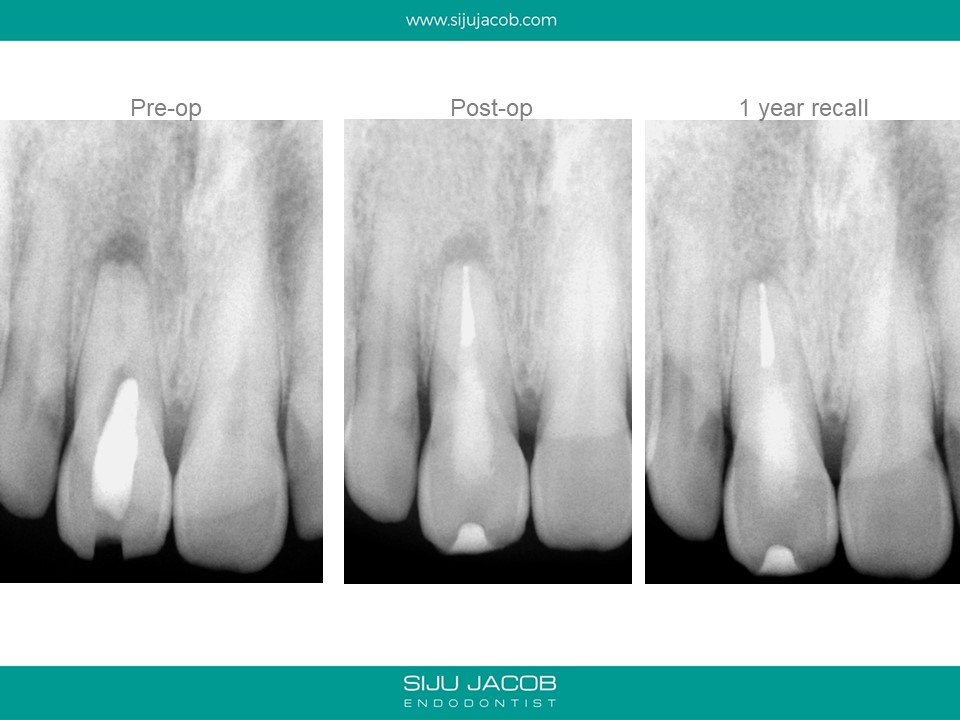

This case was referred by another practitioner who attempted to locate the canal, but couldn’t find it. The practitioner had perforated palatally in an effort to search for the canal. The perforation was supra-crestal and was sealed with Glass Ionomer. When viewed under the microscope, one can clearly see the calcified portion of what used to be the canal at one time. Once we are able to differentiate between the calcified canal and the adjacent dentine, it becomes predictable to drill apically to locate the canal.